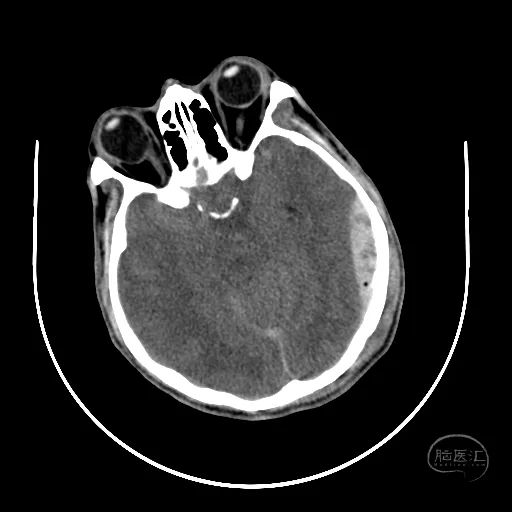

患者,男,53岁,因车祸伤1小时来诊,入院时患者烦躁,GCS评分5分,不能对答,双侧瞳孔等大等圆,直径2mm,对光反射迟钝,四肢躁动,自主呼吸尚稳定。

颅脑CT可见左侧小脑半球挫裂伤,第四脑室明显受压。

右额叶脑挫裂伤并血肿,侧脑室额角受压,脑室无明显扩张。

中线结构稍向左侧偏移。

骨窗显示枕骨粉碎性骨折,累及枕骨大孔左侧,齿突尚居中。